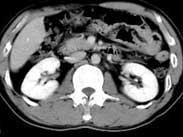

• 膽管癌

628健康網為您分享有關膽管癌的癥狀,膽管癌的治療方法,膽管癌的預防知識,膽管癌的癥狀圖片,膽管癌吃什么藥,膽管癌怎么治...